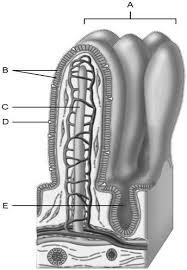

Continuation of the mesentery

D

Absorptive cells that line the intestinal tract

B

Cell type specialized to secrete mucus into the lumen of the intestinal tract.

D

Wide lymph capillary located in the villus.

C

Paneth cells are found here.

E